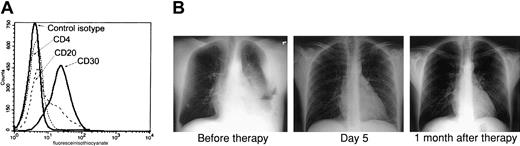

Because the combination of AZT and IFN-α exhibited a potent proapoptotic effect in PEL lines and both of these antiviral agents have been used extensively in AIDS patients, we developed a clinical protocol for this relatively rare disease. Recently an HIV-positive man, 35 years of age, presented to the emergency room complaining of shortness of breath. His absolute CD4+ T-cell count was 222/mm3 with an undetectable HIV load, and he had not taken any antiretroviral medications for several months before admission. Chest x-rays revealed a large left-sided pleural effusion and fluid accumulation in the mediastinum. Examination of this pleural fluid revealed an anaplastic lymphoproliferative process, and flow cytometry performed on tumor cells demonstrated the typical phenotype of PEL: CD4−, CD20−, and CD30+ (Figure1A). Multiple analyses of tumor cells by polymerase chain reaction (PCR) repeatedly demonstrated the presence of HHV-8 and absence of EBV (data not shown). The patient was advised of his condition, and written informed consent was obtained for our clinical protocol, which uses twice-daily parenteral AZT 1.5 g and IFN-α 5 million units. No other antineoplastic, corticosteroid, or antiretroviral agents were administered. The patient had a remarkable response with resolution of his effusion within 5 days, as demonstrated by chest x-rays (Figure 1B) and computed tomography scan (not shown). Ten days after starting parenteral therapy, he was discharged on oral AZT 600 mg daily and subcutaneous IFN-α 5 million units daily. A repeated chest film performed on the patient one month after diagnosis was clear. He continued taking AZT and IFN-α only for an additional 2 months and then stopped taking antiviral agents, although he was seen 6 months later at our AIDS clinic and was symptom free.

AZT and IFN-α induce remission in a PEL patient.

(A) Primary tumor cells (BCLM) from an HHV-8+ PEL patient demonstrate typical phenotype of PEL. Surface expression of CD4, CD20, and CD30 on 1 × 106 cells from pleural fluid was determined by FACS analysis. (B) AZT and IFN-α induce remission in the PEL patient. Left: Chest x-ray of the same patient 2 days after diagnostic thoracentesis and before therapy with twice-daily parenteral AZT 1.5 g and IFN-α 5 million units. Middle: Chest x-ray 5 days after initiation of therapy. Right: Chest x-ray 1 month after therapy.